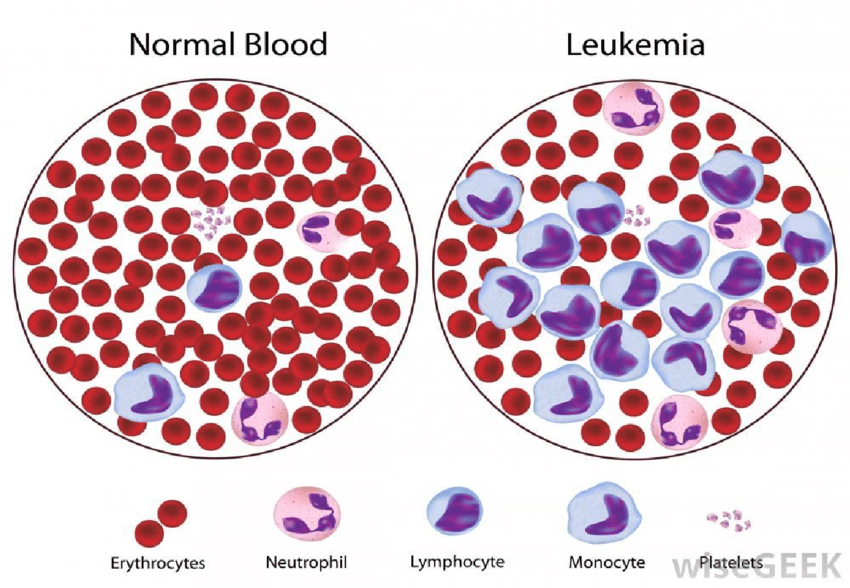

Bortezomib digunakan untuk mengobati kanker sumsum tulang.

Bendamustine bekerja dengan cara menggangu penggandaan rantai DNA pada sel kanker, sehingga terjadi fungsi sel kanker tersebut jadi terganggu.